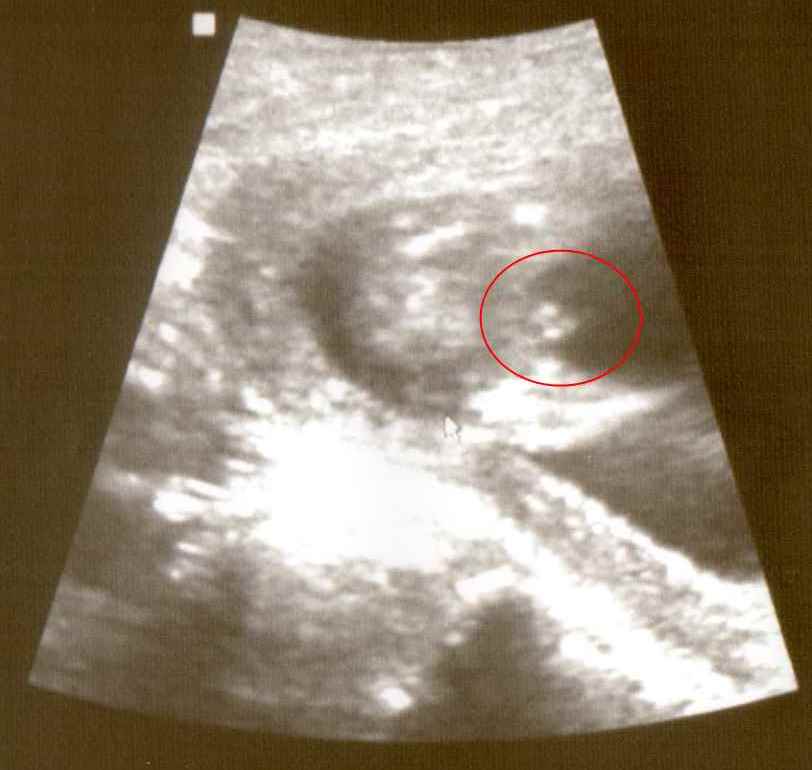

Potty shot at 15 weeks + 2 days.

Dr. said it's 50/50.

Guessing boy x

That's all boy! Def not 50/50

50/50... ya right... that is a boy!!